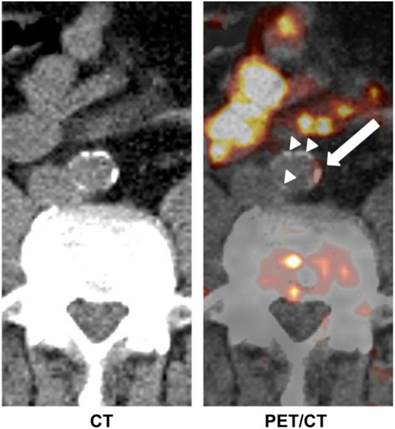

Fig 4

Transaxial 11C-acetate PET/CT images of abdominal aorta of a male patient. Tracer uptake in vessel wall coincided with calcification in some areas (white arrow), whereas other calcifications of comparable size did not accumulate 11C-acetate (white arrow heads). Adapted from reference [74].